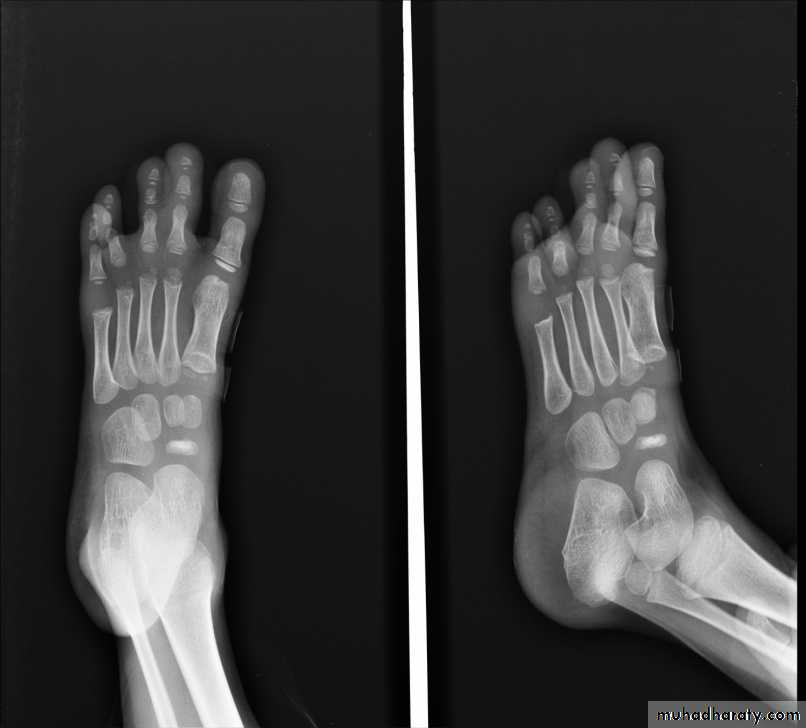

GOUT

• Radiographic features

• *Lower extremity > upper extremity; small joints > large joints

• * First MTP is most common site

• * Marginal, peri articular erosions: overhanging edge

• * Erosions may have sclerotic borders

• * Joint space is preserved

• * Soft tissue and bursa deposition

• Tophi: juxtaarticular, helix of ear

• Bursitis: olecranon, prepatellar

• * Erosions and tophi only seen in longstanding disease

• * Tophi calcification, 50%

• *Chondrocalcinosis